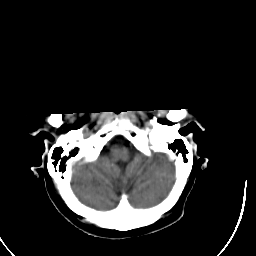

Stroke CT #3 -- Slice #2

[Home][Help][Clinical] Slice 2